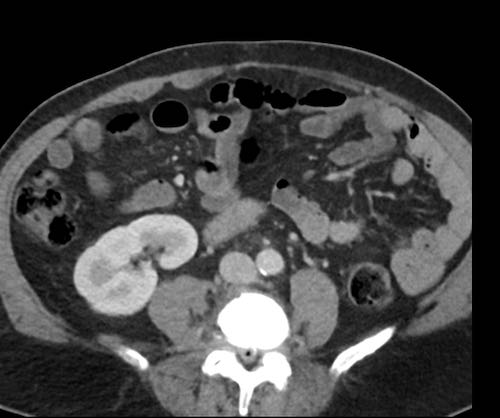

Ca lâm sàng 2

Cuộn qua các lát cắt.

Bạn có thể phát hiện tất cả các tổn thương cấy ghép phúc mạc không?

.jpeg)